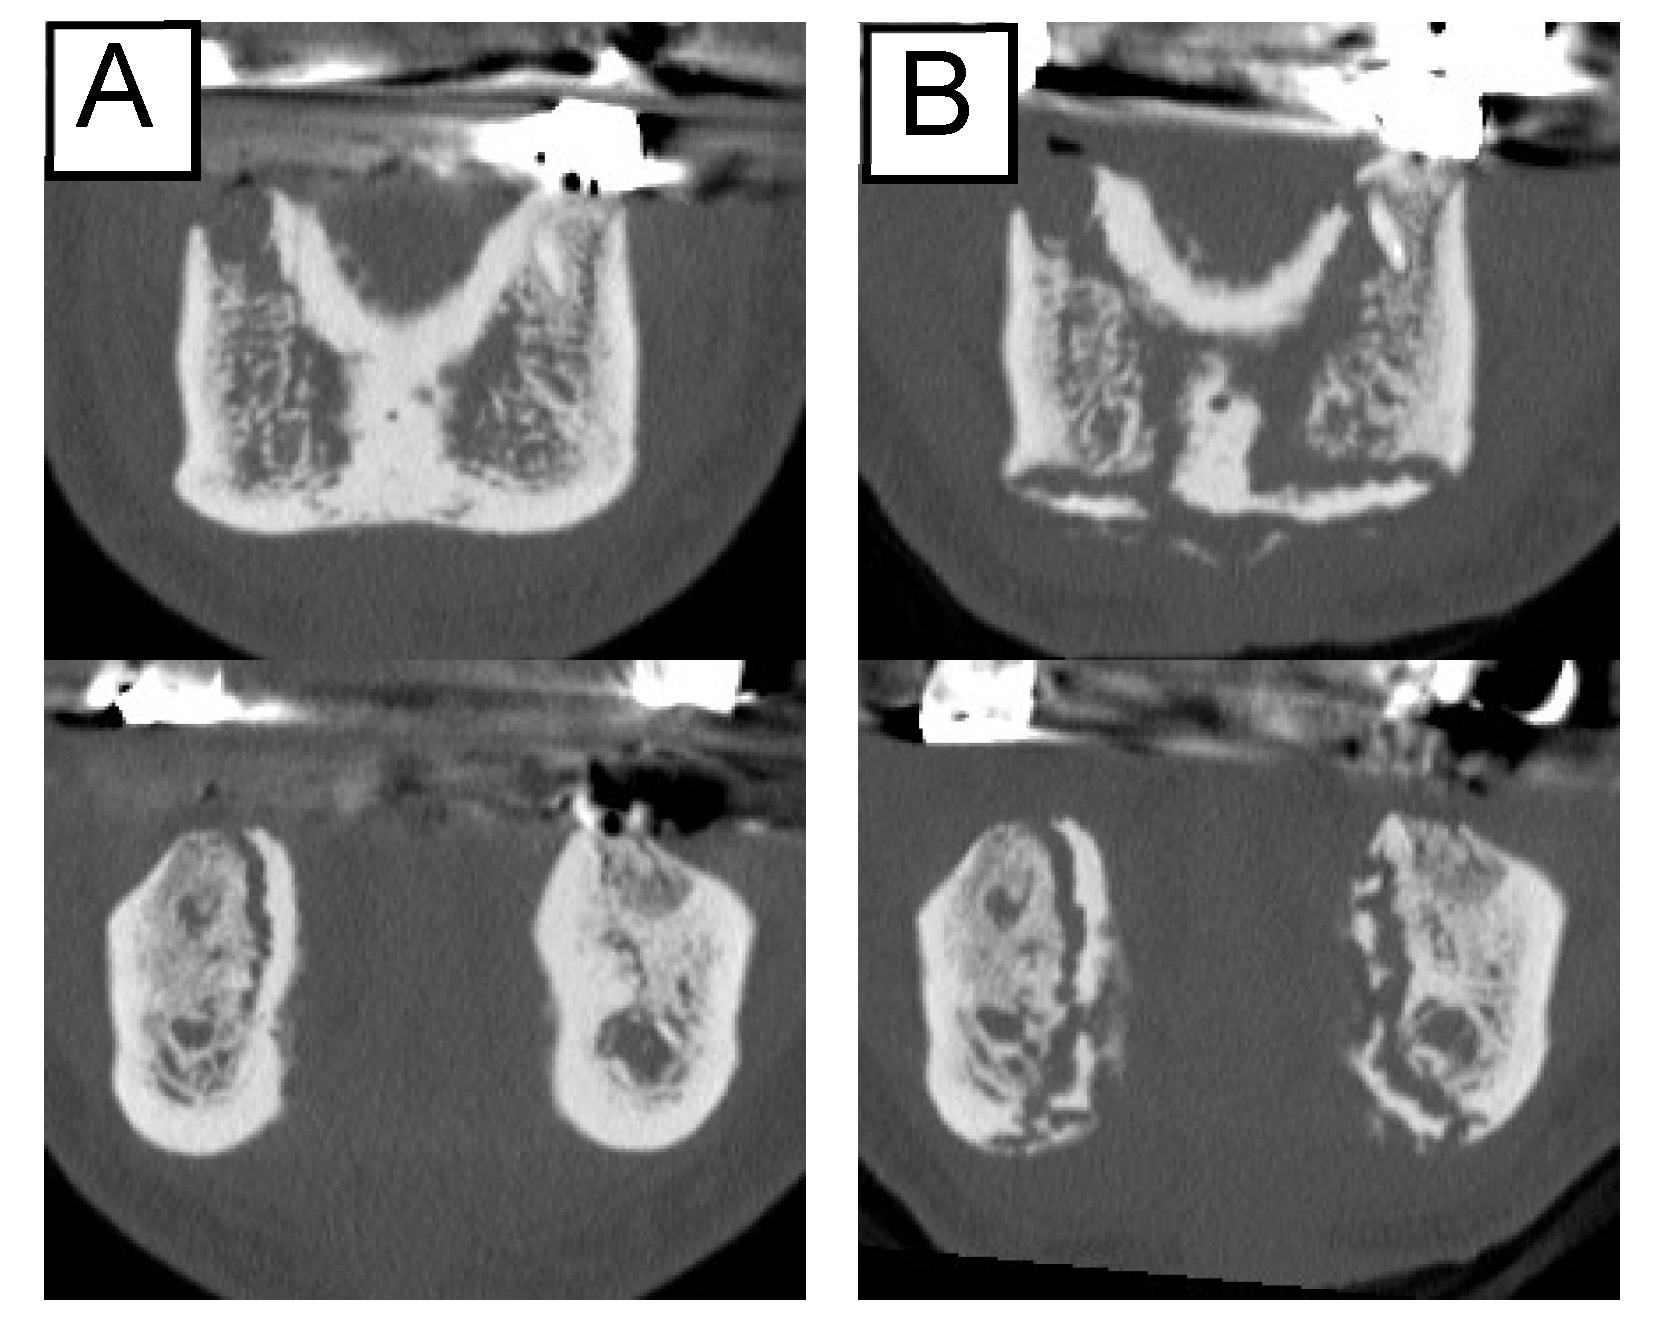

Among the 53 patients, the clinical symptoms of 15 (28.3%) disappeared or improved, while worsening was observed in 6 (11.3%). In contrast, the image findings did not disappear in any patients, and only two patients (3.8%) showed a reduction in the osteolytic area. Enlargement of the osteolytic lesion occurred in 17 (32.1%) patients (Table 2). These findings indicate that it is not uncommon for lesions to advance, even if they appear to improve clinically (Figure 2).

Figure 2.

Changes in the imaging findings. The extent of osteolysis increased despite improved clinical findings: (A) before treatment; (B) nine months later.